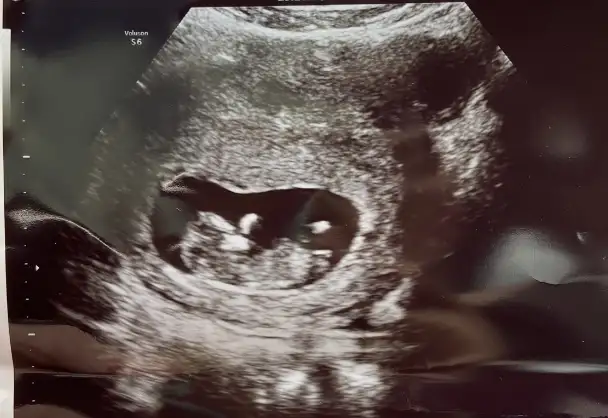

B BarbieveKen S sultansultan90 kızlar güzel haberler gelmiş tebrik ederim ikinizi de ben de dün bir bahane uydurup başka bir doktora gittim kendi doktorum kız tahmininde bulunmuştu dünkü ise erkek dedi nuba göre kız sanki ama ben bu konularda çok yeteneksizim bir de siz fallar mısınız

• CA8F6881-6F8A-438D-8796-3366DCCC9C72.webp

23,4 KB · Görüntüleme: 89